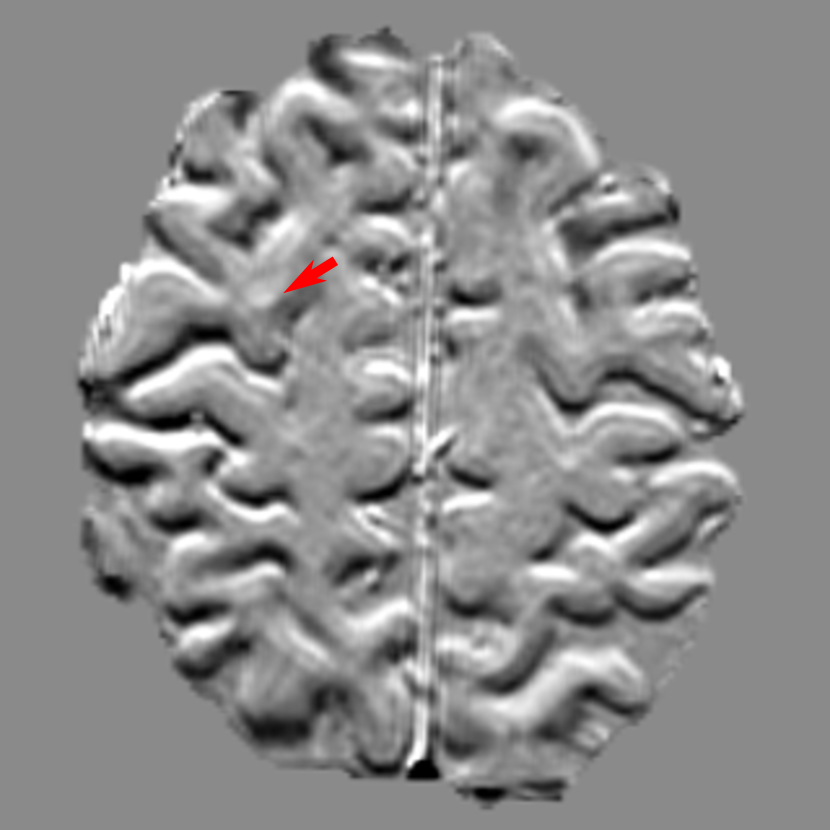

For segmentation accuracy, the mDSCs for all the TP metastases are displayed in Tab. 1. In general, the mDSCs are around 0.8. With a smaller α𝛼\alpha value, the mDSC value gets slightly smaller. The segmentation boundaries of three exemplary metastases are displayed in Fig. 8. Green boundaries are manual reference segmentation boundaries, while red (α=0.995𝛼0.995\alpha=0.995) and blue (α=0.5𝛼0.5\alpha=0.5) boundaries are segmentation boundaries of senssubscriptsens\mathcal{M}_{\text{sens}} and specsubscriptspec\mathcal{M}_{\text{spec}}, respectively. In Figs. 8(a) and (b), all the three boundaries have good consistency, with DSC values larger than 0.9. These two segmentation results are general cases for metastases larger than 0.1 cm3. Fig. 8(c) is one example where DeepMedic+ achieves lower DSC values. The tumorous region in this case is difficult to define in single-sequence data as some part of the whole tumor has necrosis after treatment. In addition, the active parts, which are enhanced by contrast agents, are separated in many axial slices. Therefore, senssubscriptsens\mathcal{M}_{\text{sens}} and specsubscriptspec\mathcal{M}_{\text{spec}} both segment the active parts as two separated metastases. As a consequence, the DSC values are low. Nevertheless, senssubscriptsens\mathcal{M}_{\text{sens}} segments the active parts better than specsubscriptspec\mathcal{M}_{\text{spec}}. Tab. 1 indicates that senssubscriptsens\mathcal{M}_{\text{sens}} achieves better mDSC values than the baseline DeepMedic, while specsubscriptspec\mathcal{M}_{\text{spec}} is slightly worse. Since the union of senssubscriptsens\mathcal{M}_{\text{sens}} and specsubscriptspec\mathcal{M}_{\text{spec}} segmentation masks is used in our ensemble learning, the good segmentation of senssubscriptsens\mathcal{M}_{\text{sens}} is preserved.

Refer to caption

(a) 0.941, 0.916

(b) 0.910, 0.910

(c) 0.596, 0.133

Figure 8: Segmentation boundaries of three exemplary metastases. Green boundaries are manual reference segmentation boundaries, while red solid and blue dotted boundaries are segmentation boundaries of senssubscriptsens\mathcal{M}_{\text{sens}} and specsubscriptspec\mathcal{M}_{\text{spec}}, respectively. The DSC values of each metastasis volume are displayed on the left and right in the subscaptions for senssubscriptsens\mathcal{M}_{\text{sens}} and specsubscriptspec\mathcal{M}_{\text{spec}}, respectively. Zoom in for better visualization.